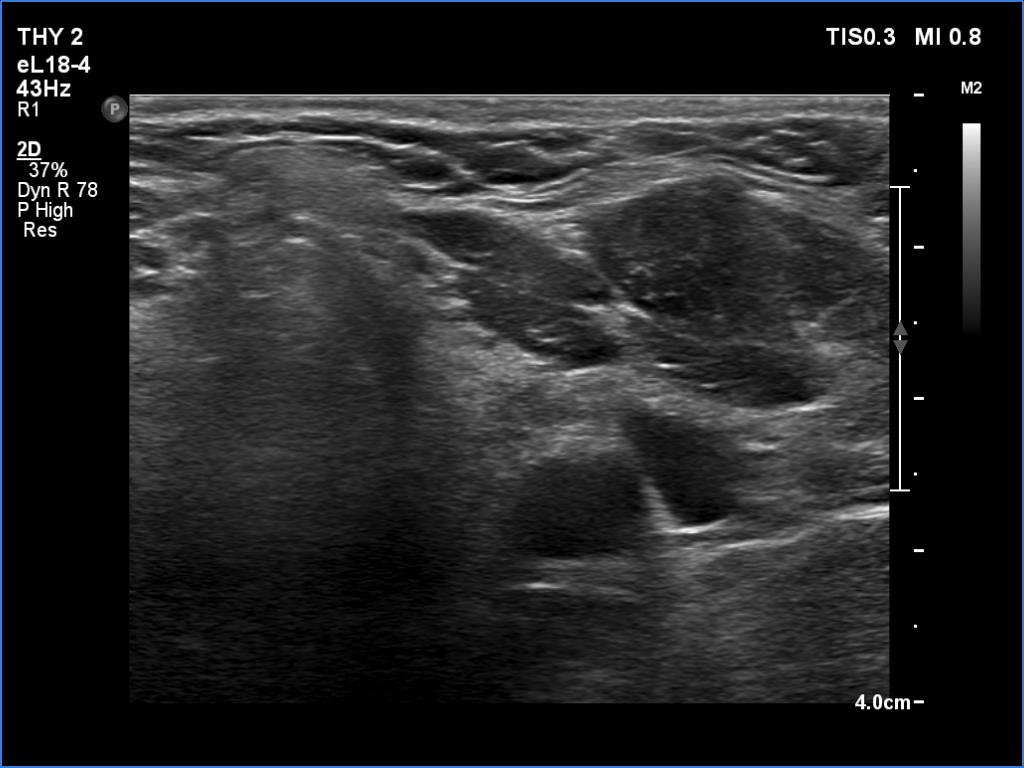

A patient operated on Graves' disease then received radioiodine therapy - case 321

After the surgery before the radioiodine treatment

After the radioiodine treatment

The patient had a recurrent hyperthyroidism 15 years after a bilateral subtotal resection performed because of relapsing Graves disease. Several months after the first visit, the patient underwent on radioiodine treatment. The right images were recorded 5 years after the isotope therapy.

In surgically treated thyroids, the histopathological findings must be taken ito account in order to avoid mispretating discrete lesions. If the previous histopathology did not find nodule than an ambiguous lesion is very rarely a true nodule.

The echonormal areas which surround the hypoechoic lesion can be tracked up, down and sideways, therefore these do not correspond to thyroid tissue but to connective tissue.